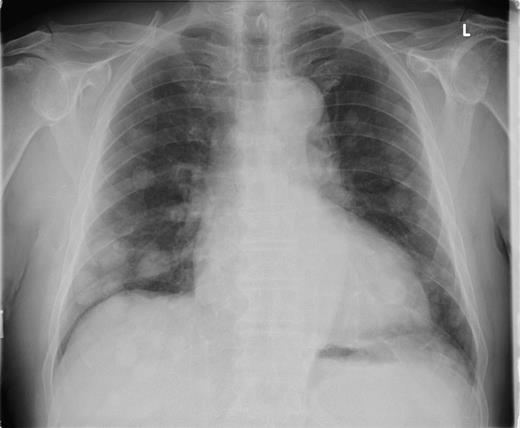

Seventeen months following initial presentation, the patient developed a mass in the right axilla. In addition, subsequent plain chest radiograph (Fig. 4) and CT of the thorax showed multiple pulmonary metastasis. An axillary clearance was performed and one of the ten nodes confirmed metastatic disease. Shortly after this, the patient suffered an intracranial haemorrhage into the right internal capsule. Over the last 2 years the patient has remained only mildly short of breath due to his pulmonary metastasis and was improving neurologically. At a recent review, the patient showed features of deterioration due to the pulmonary metastasis.

Plain chest radiograph taken 17 months after excision of the primary lesion showing multiple pulmonary metastasis.